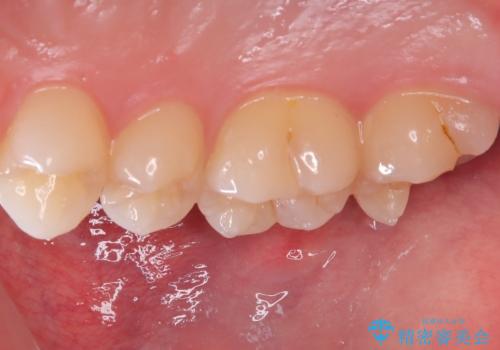

左上一番奥の歯の頬側に実質欠損を伴う虫歯が存在したため、セラミックインレーでの治療となりました。

上顎左側第二大臼歯頬側面から遠心面、咬合面にもう蝕が波及していたためアンレー形態となりました。

清掃しずらい箇所ではあるため、汚れが付きづらい適合性のよいセラミック素材を選択しました。

セラミックアンレーセット時、ラバーダム防湿を行っています。